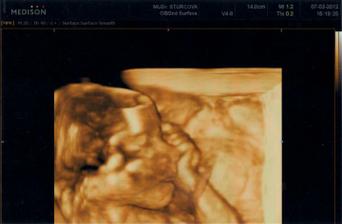

7.3.2012 konečně nstal den velkého ultrazvuku. Už jsem se nemohla dočkat. Dva dny jsem necítila pohyby tak jsem byla už nervózní ale včera začalo zase kopat tak už je to fajn. Všechna vyšetření moči i krve mám naprosto v pořádku. Na velkém utz vše dopadlo taky dobře. miminko má vše v pořádku. Je nádherné a krásně se tam vrtělo. Vyplazovalo na nás jazýček, olizovalo si ručičku a dávalo si pořád kolínka k hlavičce. Je to moje zlatíčko. Když se nás zeptala jeslti chceme vědět pohlaví tak manžel ani nezaváhal a hned že JO. Tak nám tedy na 90% řekla že to bude holčička. Mě se rozzářily oči, tak nakonec to bude má vytoužená Nikolka..... Manžel je rád , jen uvažuje jak jí naučí modelařit a lítat s letadlama, ale to prej půjde. Jsem ráda že je zdravá. Za týden jdeme ještě na jeden utz a pak na srdíčko. Snad bude i tam vše ok. Jinač nám nahrála ultrazvuk na DVD ve formátu 3D tak to bylo nádherné. a ty fotky jsou úžasné. Stálo to 800,- ale nelituji. šla bych do toho zase.... ten černobílý to není ono to je jen takový malý kostliveček ale to 3D to je vážně už krásné mimi... NAŠE MIMI 🙂 už se na tu mojí princeznu těším....